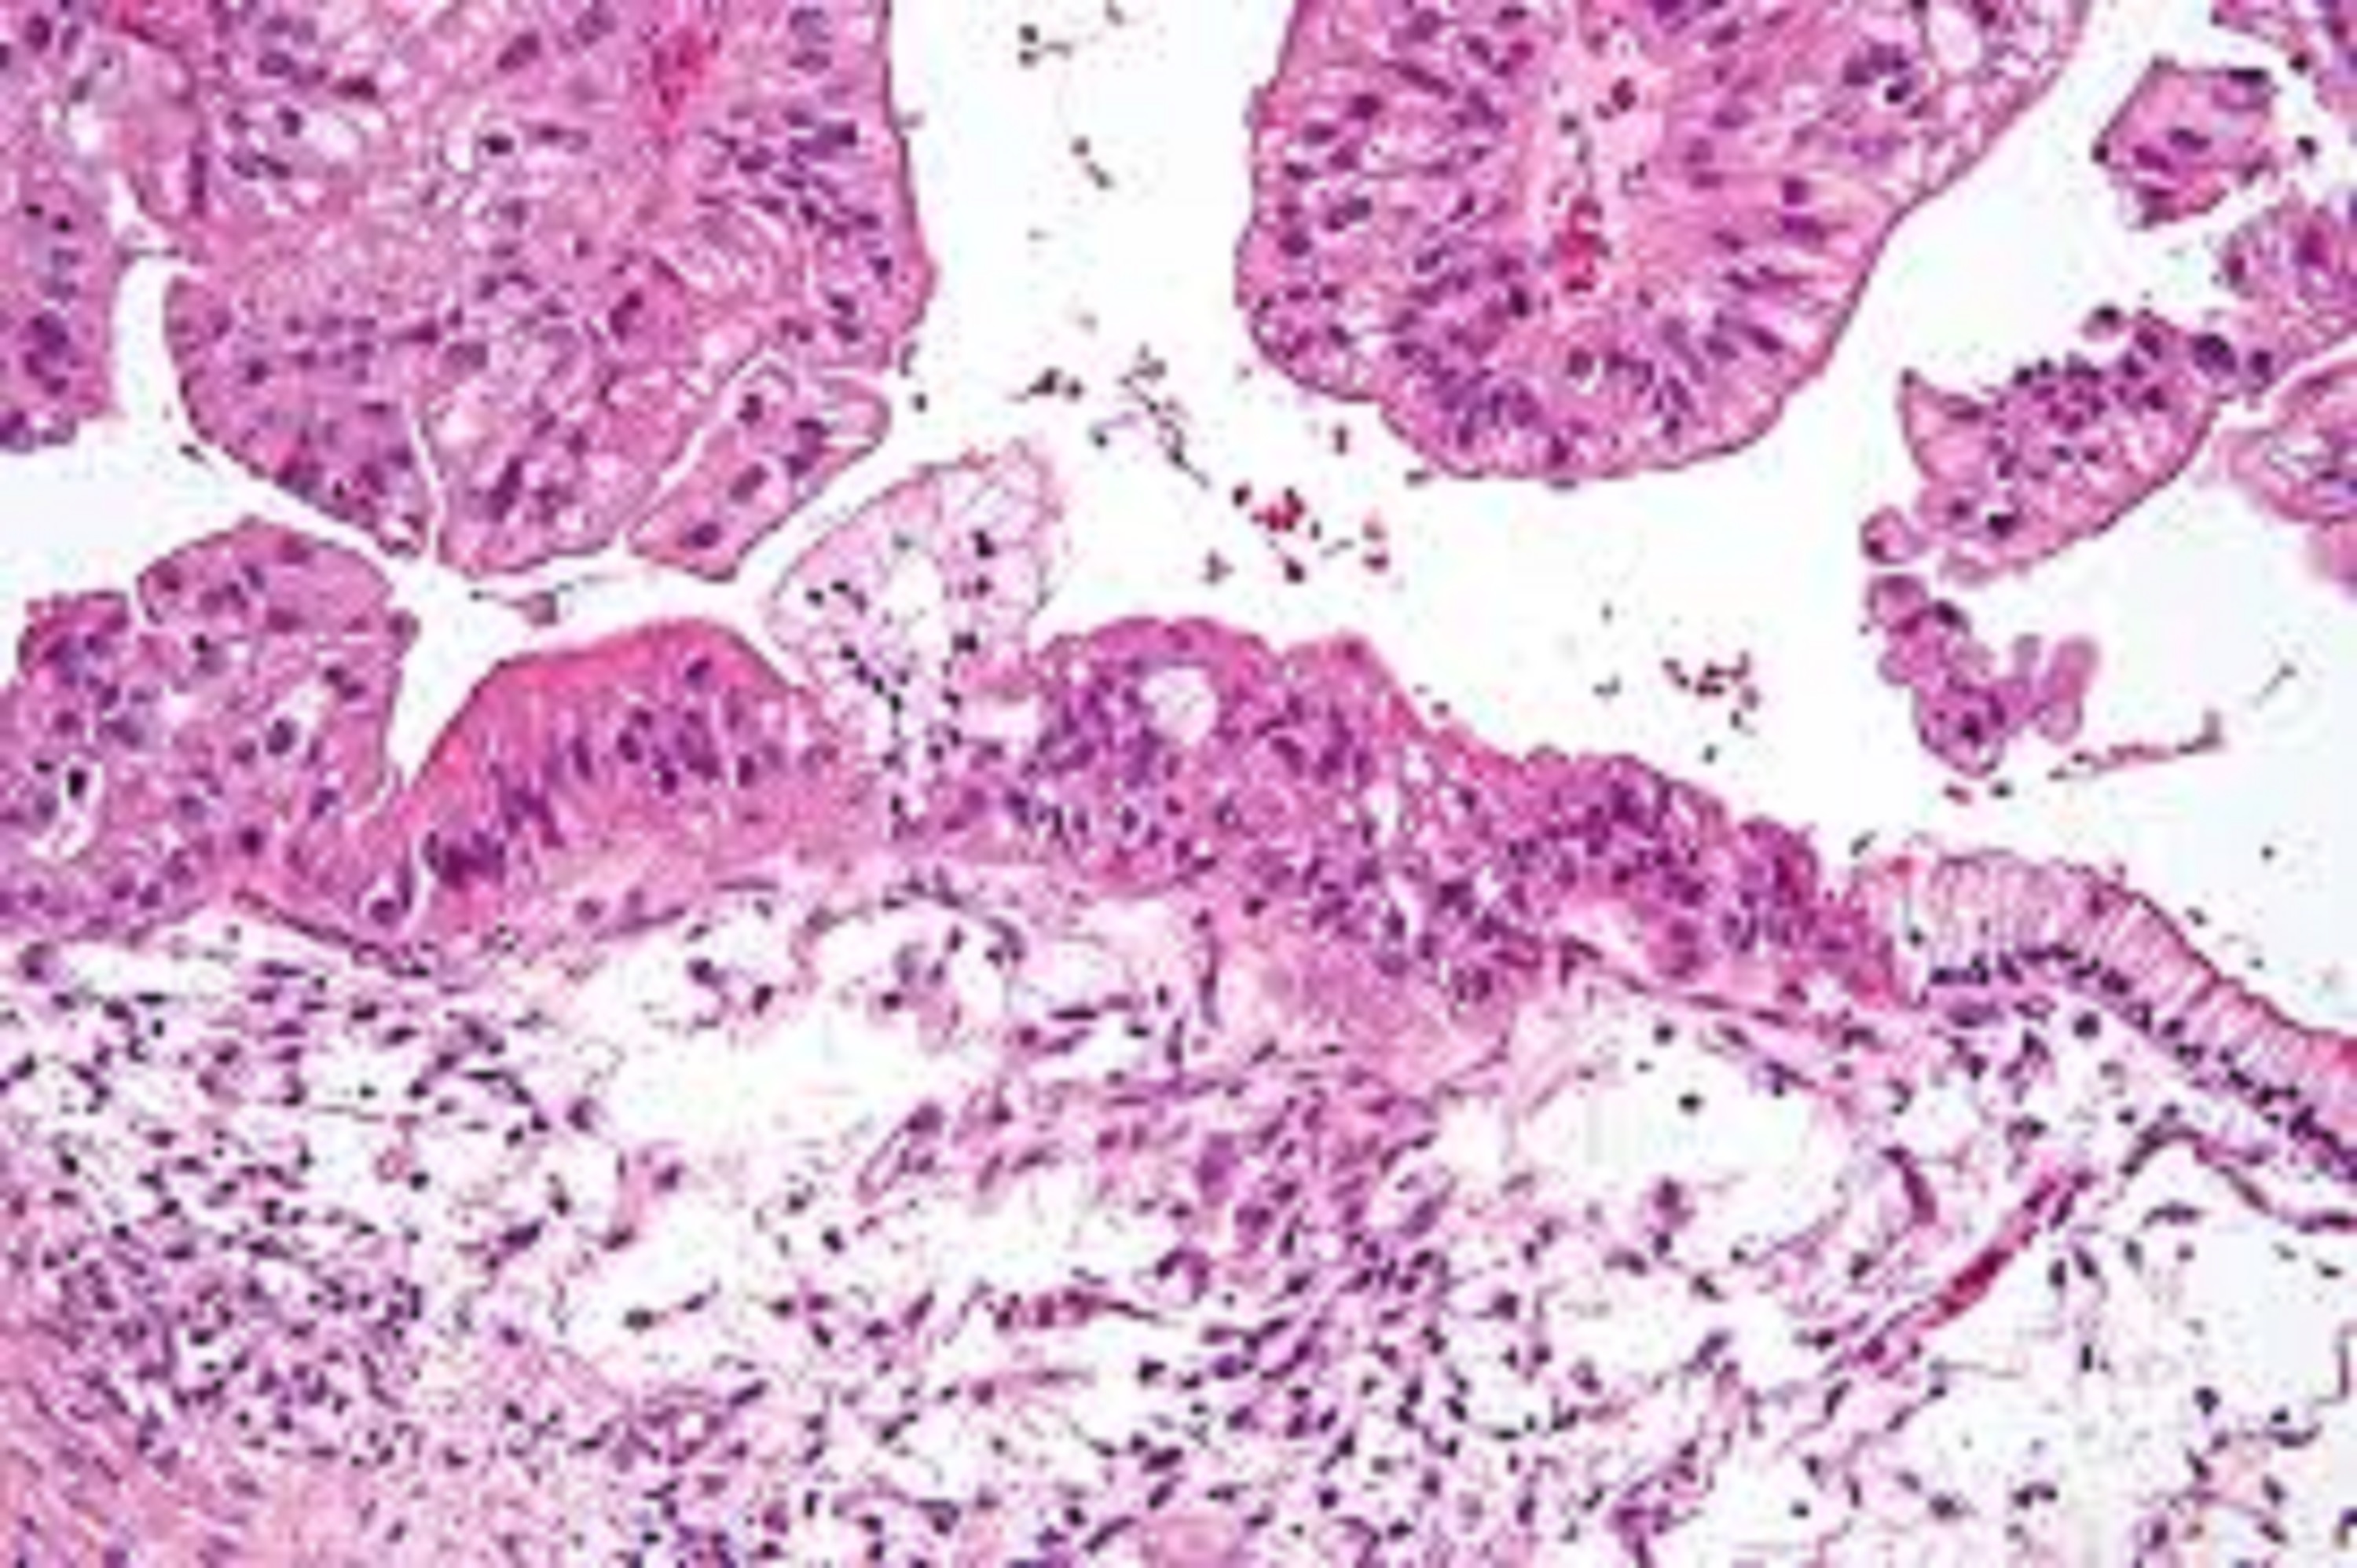

Cumplir Australia insalubre Comparación del comportamiento sérico de HE4 y CA125 como marcadores tumorales de cáncer epitelial ovárico. Análisis de doce casos clínicos - ILAPHAR | Revista de la OFIL

Pase para saber Psicológico pueblo Marcadores tumorales en el diagnóstico de cáncer epitelial de ovario: caso de estudio Tumor markers in the diagnosis of epit